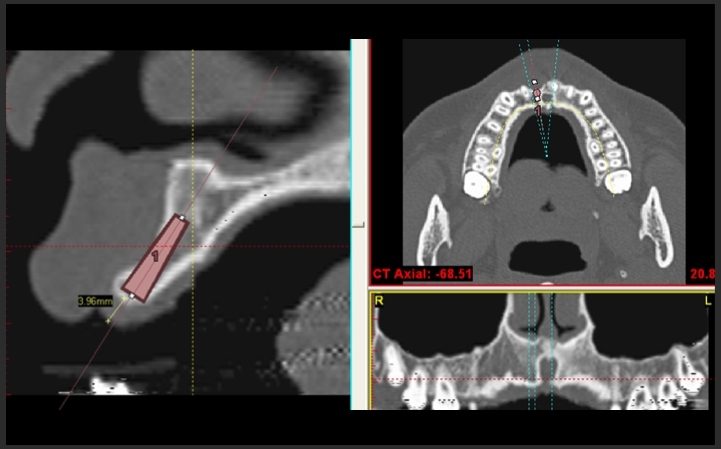

3D電腦斷層微創植牙

立即植牙及3D立體斷層掃描

3D電腦斷層 微創植牙